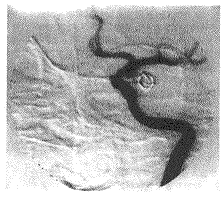

1.1 病例资料:例1,女性,35岁。因头痛、头晕和视力下降,经头颅MRI检查疑颅内动脉瘤收入院。既往无蛛网膜出血史。入院神经系统检查(-)。头颅MRI扫描显示左鞍旁类圆形影,有明显增强效应。入院后第2天行全脑血管造影,证实为左颈内动脉海绵窦段囊状动脉瘤。动脉瘤直径为15 mm,瘤蒂窄小,瘤体指向左后外方(图1)。

图1 左颈内动脉造影(正斜位)

显示左颈内动脉海绵窦段囊状动脉瘤。动脉瘤直径15 mm,瘤蒂窄小,瘤体指向左后外方